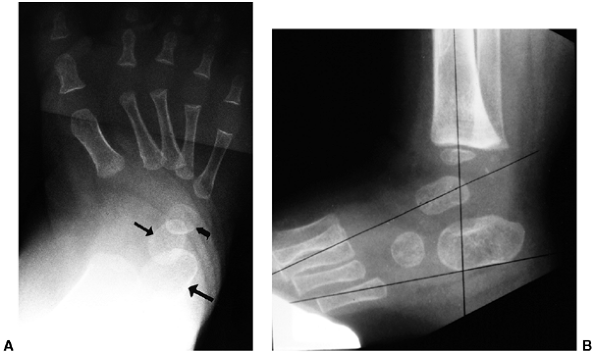

The anterioposterior view is obtained with the foot pressed against a

maximally and held in a position of external rotation (37,45) (Fig. 30.8).

The talus to first metatarsal angle is measured on both the

anteroposterior and lateral views, with increasing angles indicating

more severe deformity. As the navicular is not ossified, there is no

direct measurement of the position of this bone relative to the long

axis of the talus (46). The axis of the talus

and the calcaneus usually converge, and the axis of the talus and the

first metatarsal form a straight line in the healthy state. The degree

of divergence from this linear alignment represents the intrinsic

deformity of the clubfoot (46). With

dorsiflexion, the long axis of the talus and the calcaneus remain

parallel, and the calcaneus remains plantar-flexed relative to the long

axis of the talus (Fig. 30.8). The alignment of the calcaneus and the cuboid is assessed on the anterioposterior view.

![]() |

Figure 30.8 A: Simulated weight-bearing anteroposterior radiograph of clubfoot. The talus (small straight arrow) and calcaneus (large straight arrow)

are parallel, rather than divergent. The metatarsals are markedly adducted in relation to the talus. The cuboid ossification center (curved arrow) is medially aligned on the end of the calcaneus, rather than in the normal straight alignment. B: Maximum dorsiflexion lateral radiograph of clubfoot. The talus and calcaneus are somewhat parallel to each other and plantar-flexed in relation to the tibia. |